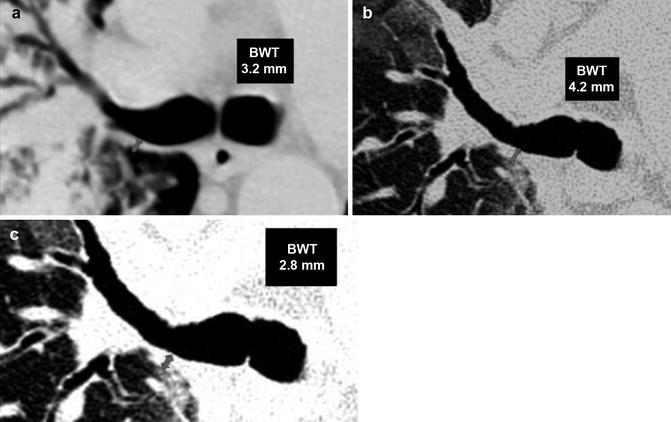

Fig. 16.

Thin-section CT findings in bronchiectasis. (a) The so-called signet ring sign (circle), a bronchus with an internal diameter greater than the diameter of the adjacent pulmonary artery. (b) Sagittal reconstruction shows a bronchiectatic bunch of grapes in the middle lobe. (c) Sagittal reconstruction shows lack of airway tapering >2 cm distal to point of bifurcation, bronchial wall thickening, and bronchi abutting the pleural surface. The wall thickness evaluation varies depending on slice thickness and window levels. (d) Coronal reconstruction shows lack of airway tapering and mosaic attenuation pattern